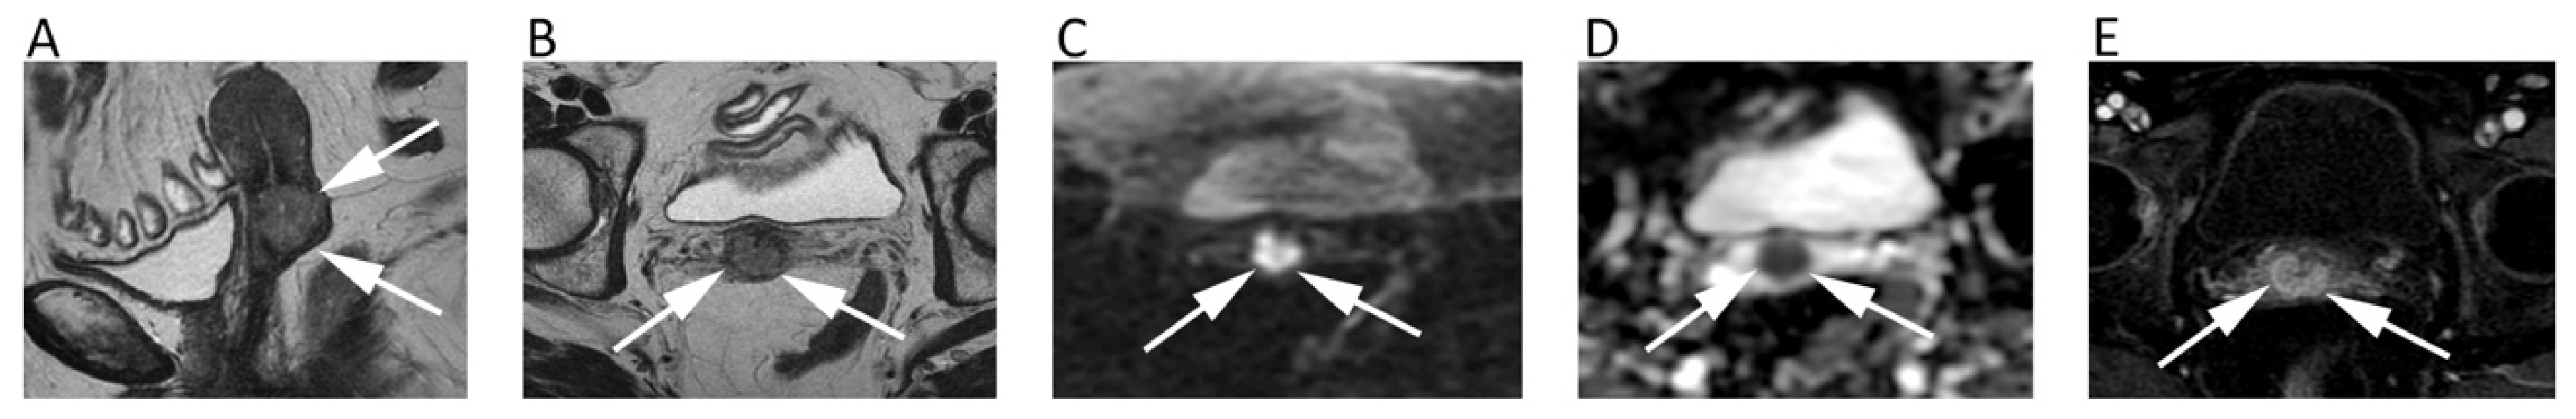

An MRI is part of both primary staging and restaging of rectal cancer, allowing one to stratify treatment by identifying those patients at risk of local recurrence. DWI can be helpful in primary staging of rectal cancer in adjunction to conventional sequences, applying at least two b values and with b = 1000 generally being used as the highest b-value. A recent study reported an improved specificity (63.2% to 75.9%) of MRI in detecting perirectal infiltration by adding DWI to T2-weighted [53]. According to the recent international guidelines, DWI should be included in MRI protocol, especially for restaging rectal cancer to differentiate complete from partial response, with still no consensus on the added value of DWI in the assessment of primary T and N-staging [54]. Indeed, a meta-analysis on the restaging of rectal cancer of 1556 patients after chemo-radiotherapy showed the high sensitivity of DWI (83.6%), with an improvement of the negative likelihood ratio [55]. Further, previous studies have shown the added value of T2-weighted and DWI findings combined with endoscopy, leading to a post-test probability of 98% for predicting complete response after chemo-radiotherapy [56]. Nevertheless, DWI alone is not accurate enough in restaging rectal cancer; thus, the conjunction with standard sequences is recommended. Notably, although the evaluation of ADC changes during treatment has shown to be promising to assess treatment response (Figure 7), DWI should be only qualitatively assessed, with ADC quantification having still no role in clinical practice due to a lack of protocol standardization and agreed cut-off values [54].

Figure 7.

MRI scans of a 66-year-old female patient with rectal cancer at the initial diagnosis and two months later after neoadjuvant chemotherapy. Axial T2w image (A) and axial post-contrast fat-suppressed 3D GRE T1w image (B) show the tumor along the posterior rectal wall (arrows) with high signal intensity on the axial b = 600 DWI image (C) and low ADC (mean ADC: 0.651 × 10−3 mm2/s) on the corresponding ADC map (D). Post-treatment axial T2w image (E) shows the reduction in size of the lesion (arrowheads) with decrease of contrast enhancement (F) and slight increase of ADC values (G,H).